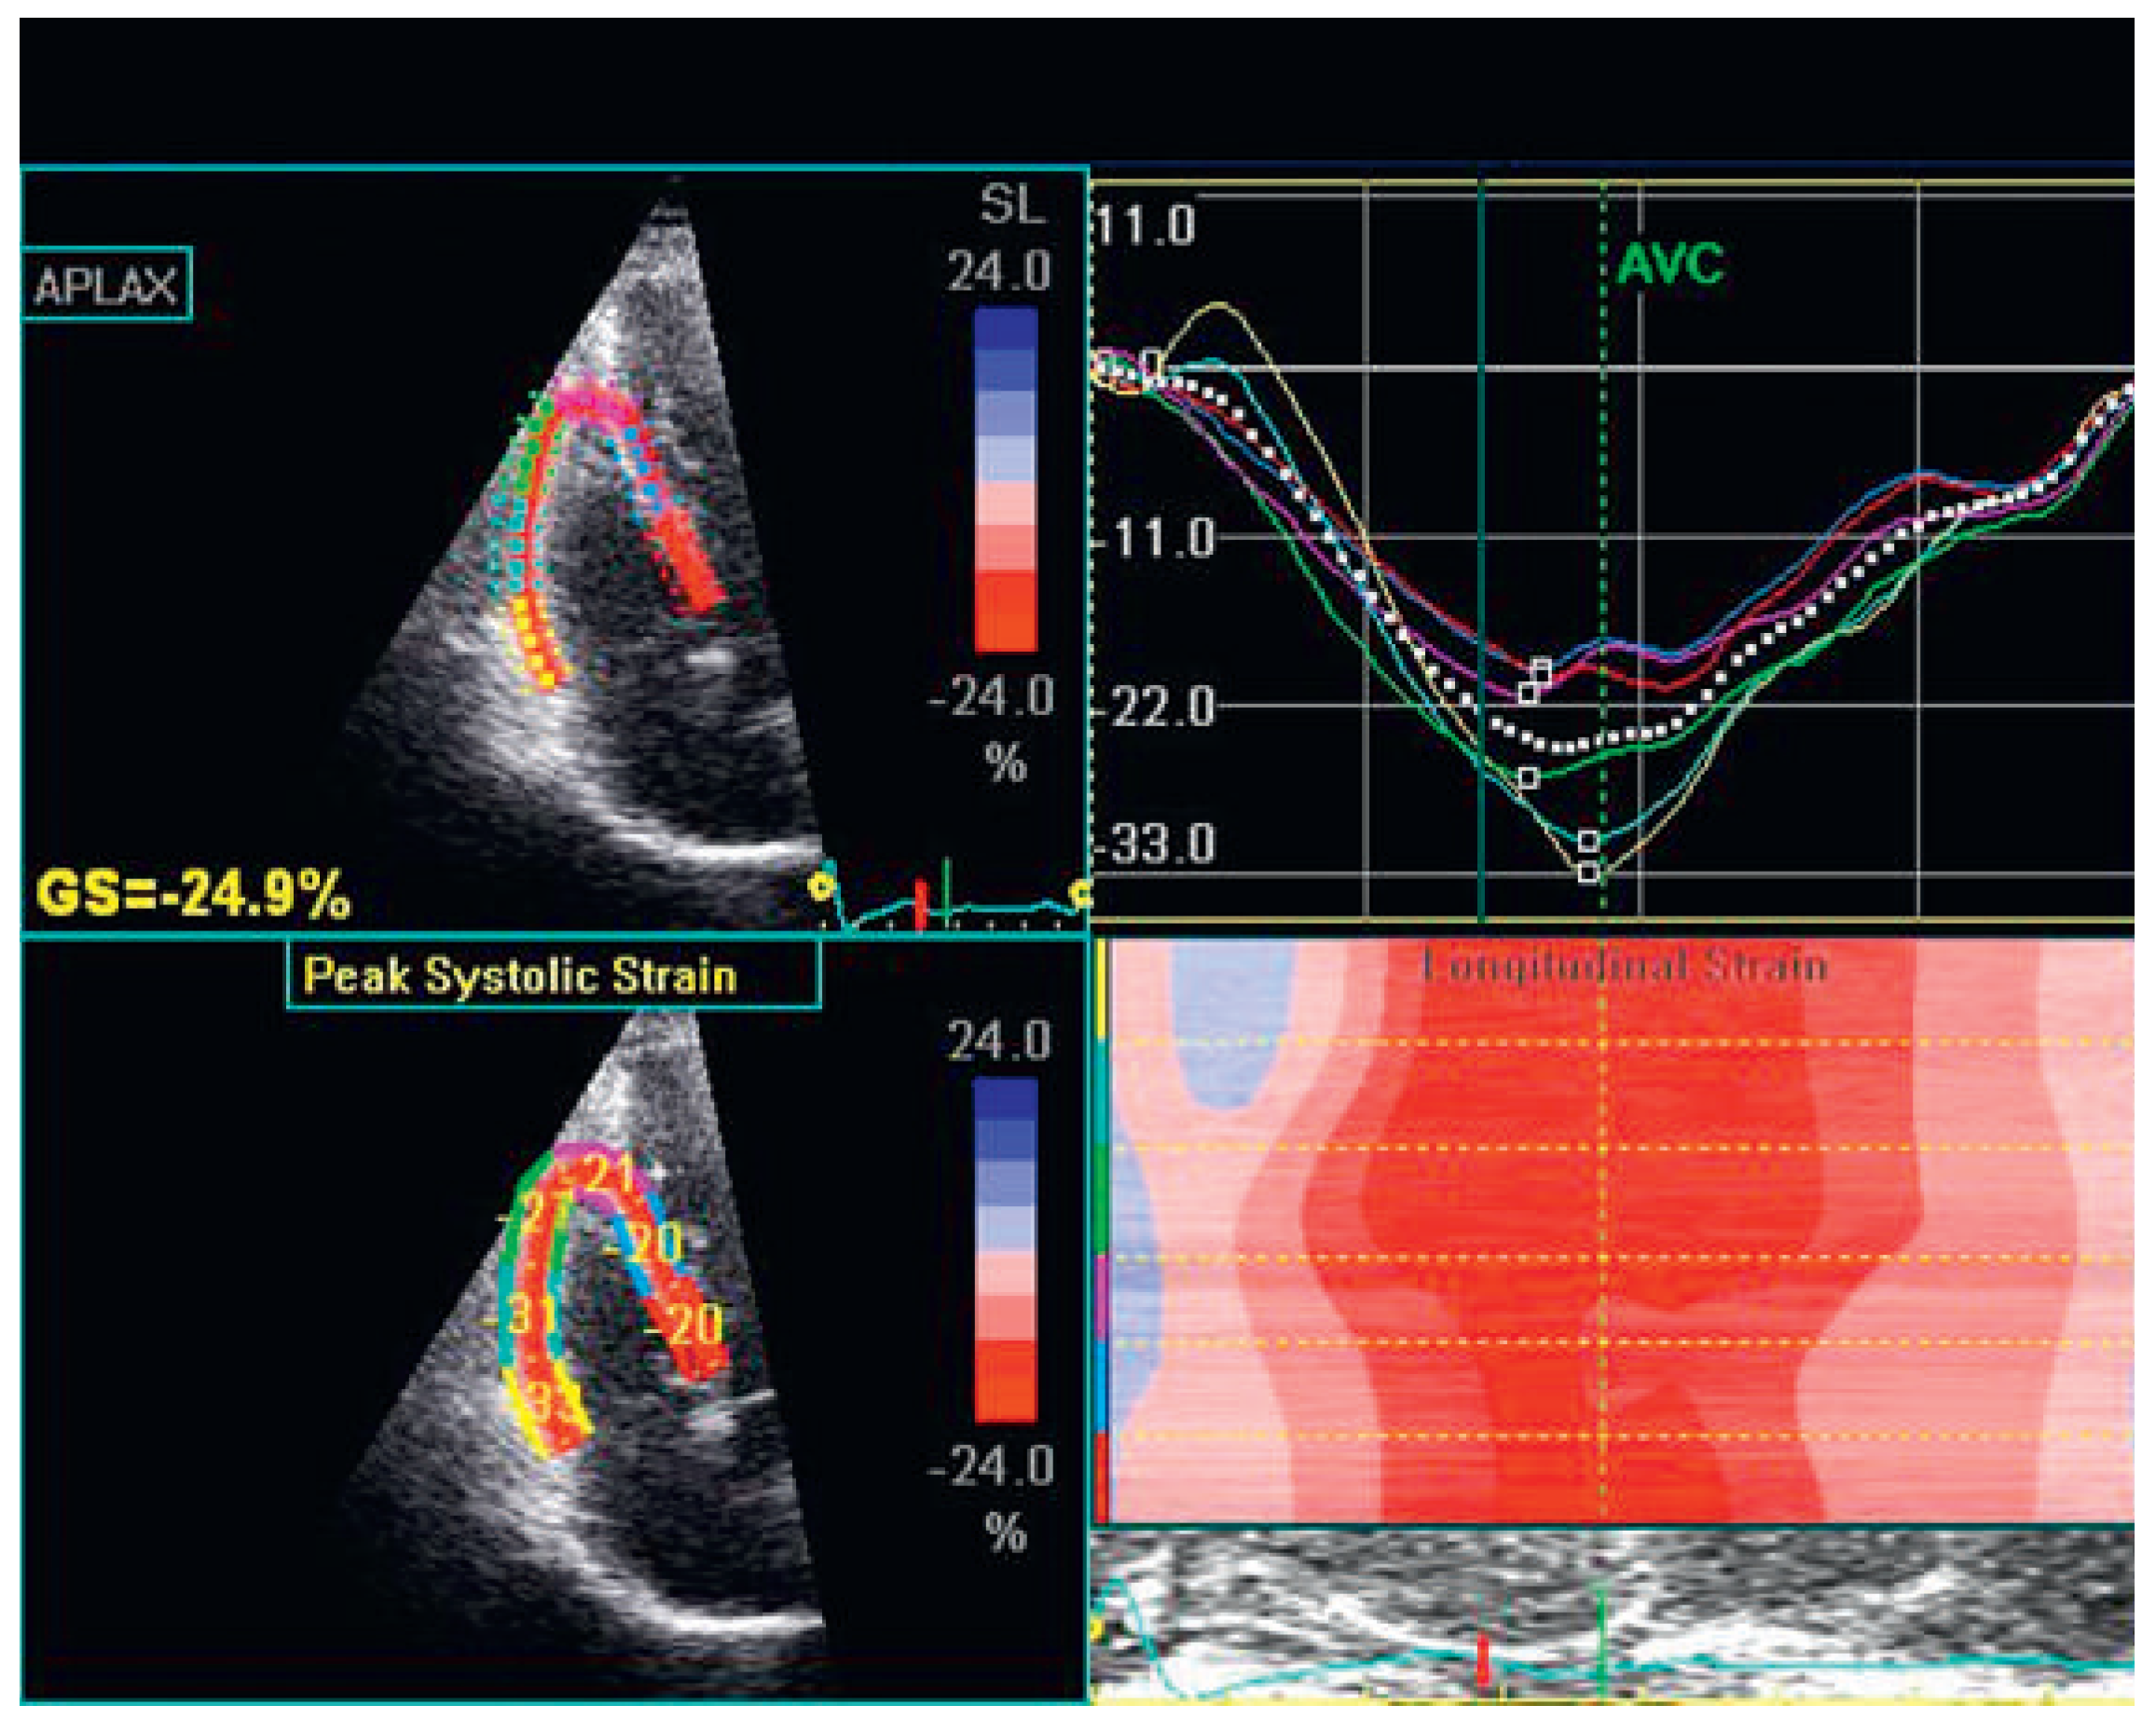

Speckle tracking and three-dimensional echocardiography